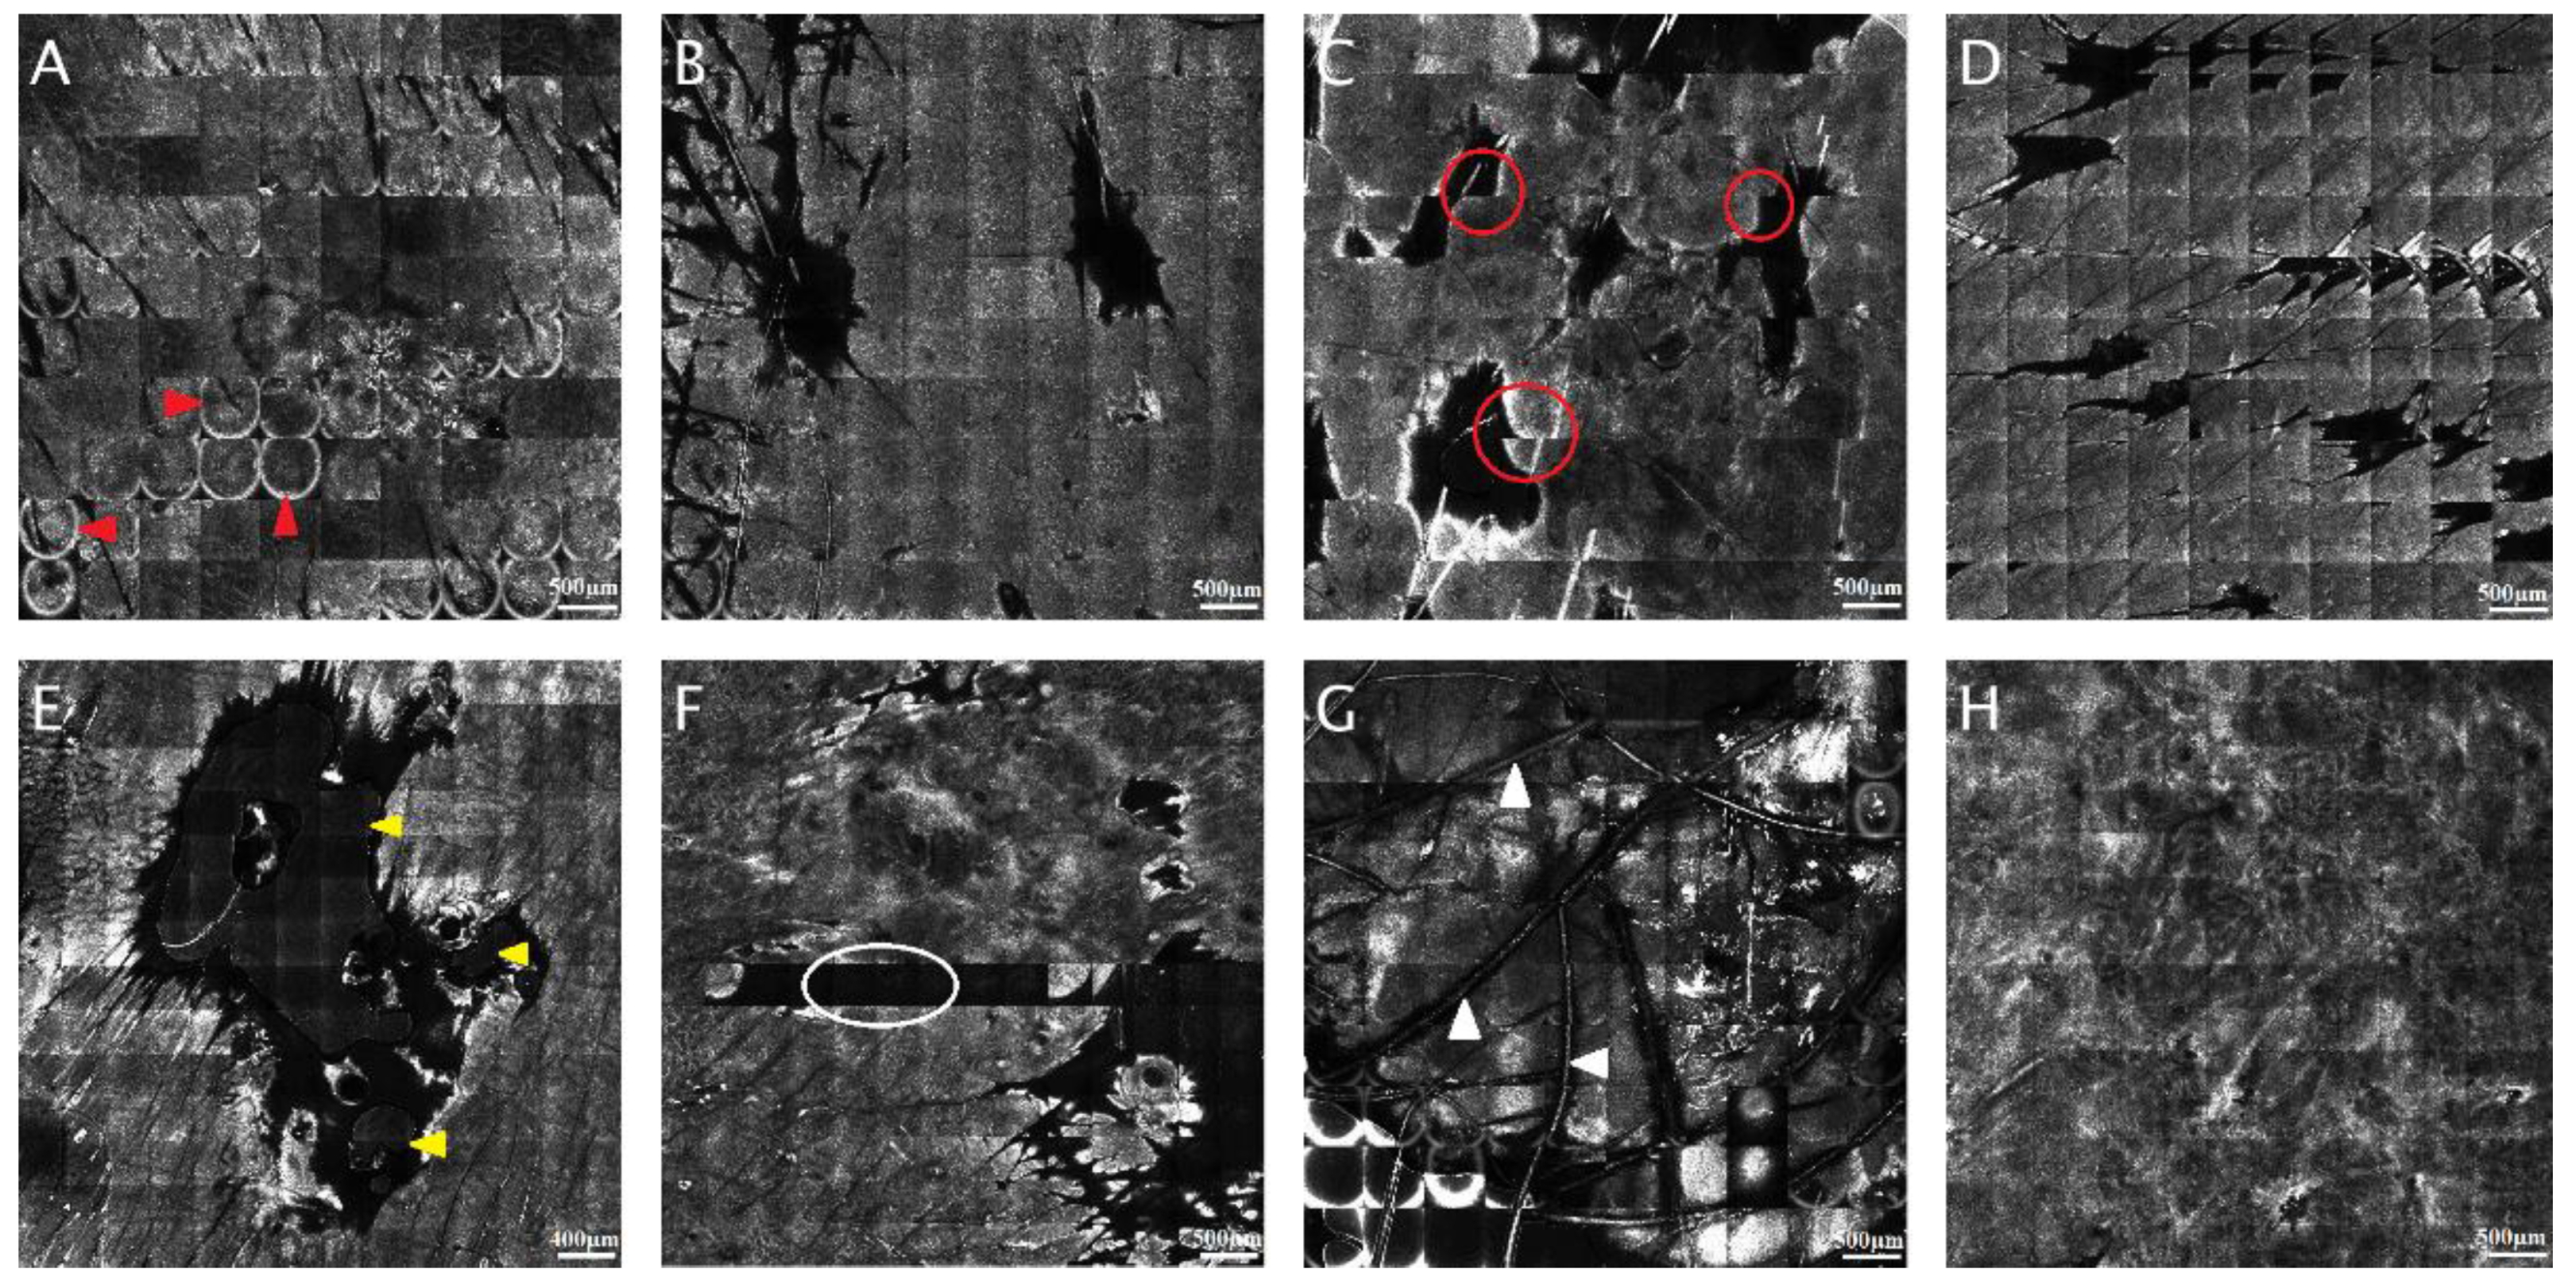

3.1. Quality Assessment of Reflectance Confocal Microscopy Composite Images (Mosaics)

3.2. Automated Delineation of the Dermal-Epidermal Junction

3.3. Convolutional Neural Networks and Classification and Regression Trees for Skin Lesion Identification on Static RCM Images